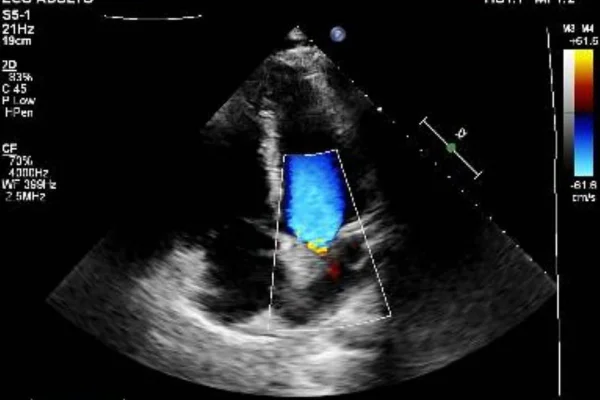

O influenciador Vittor Fernando reapareceu nas redes sociais neste sábado (25/10) para relatar momentos de terror vividos durante uma tentativa de assalto no Rio de Janeiro. O criador de conteúdo contou que foi atingido por dois tiros, sendo que um dos projéteis ficou alojado em seu coração.

“Nunca vivi dias tão assustadores… Eu vi a morte de perto, bem perto mesmo, com uma bala que entrou perto do meu peito, estilhaçou e foi parar dentro do coração”, escreveu o influenciador em uma publicação nas redes sociais.